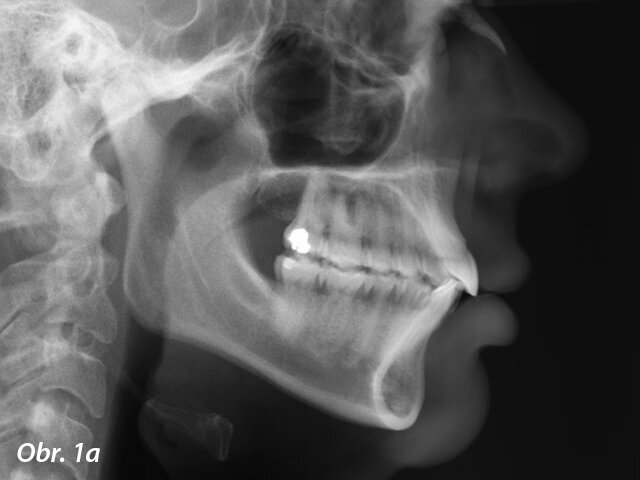

Pacientka 1 – Počáteční telerentgen a panoramatický rentgen.